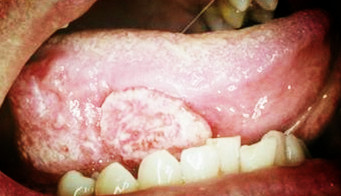

舌癌

舌癌是口腔颌面部常见的恶性肿瘤,目前舌癌主要是以手术为主的综合治疗,一般应行原发病切除及颈部淋巴结清扫术,在手术治疗过程中,如何确定颈淋巴清扫的范围?